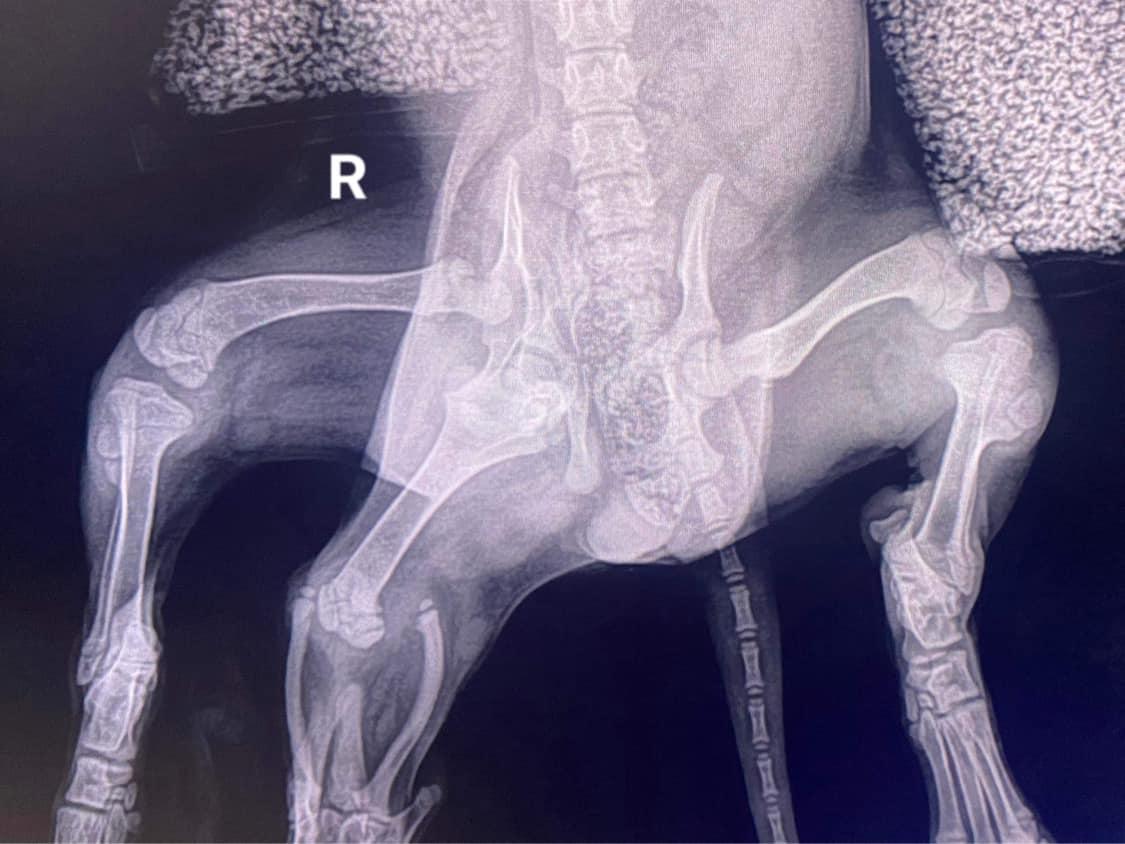

أنقذ ملجأ للحيوانات في المملكة المتحدة أنثى جرو ولدت بستة أرجل وتشوهات أخرى، وشارك ملجأ “Greenacres Rescue” في بيمبروكشاير على “فيسبوك”، أن أنثى جرو بستة أرجل تم تسليمها إلى عيادة بيطرية محلية في 27 سبتمبر بعد العثور عليها مهجورة في موقف للسيارات في موقع “Pembroke Dock” التابع لمزرعة “Ebbs Acres Farm”.

وحثت هيئة الإنقاذ المالك أو أي شخص لديه معلومات عن الحيوان التقدم بها، وقالت إنهم في هذه الأثناء «سيبدأون خطة التشخيص والعلاج مع أطبائنا البيطريين». وأضاف المنقذون: «نأمل أن تتمكن من عيش حياة طبيعية، إذا أثبتت اختباراتها أنها إيجابية».

وكتبت “Greenacres” في تحديث على “فيسبوك” في اليوم التالي أن أنثى الكلب بصحة جيدة.